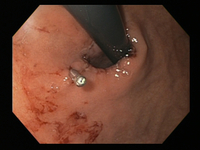

A through-the-scope clip deployed in the centre of the lesion (no previous adrenaline was infused in this case)

From the collection of Juan Carlos Munoz, MD, University of Florida